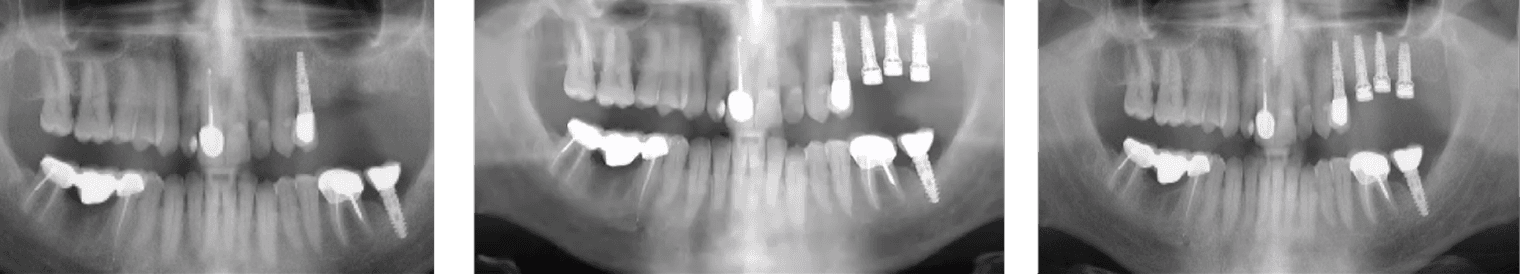

A 70-year-old heavy smoker presented with a fully edentulous mandible and clinically poor bone quality. Six implants were placed, each fitted with a MED healing abutment to enhance bone regeneration and support early osseointegration. Despite the compromised bone condition and smoking-related healing challenges, the patient demonstrated an excellent biological response throughout the recovery phase.

After only 45 days, radiographic assessment confirmed successful osseointegration across all six implants, allowing for full-arch prosthetic restoration. The patient received a stable mandibular bridge within a significantly shortened treatment period. The use of MED healing abutments contributed to rapid bone maturation, improved implant stability, and an accelerated rehabilitation process even in a high-risk, heavy-smoking patient.

A 55-year-old heavy smoker underwent a comprehensive maxillary rehabilitation procedure that included sinus lift and ridge preservation following tooth extraction. Three months post-extraction, implant placement was performed along with crestal sinus augmentation using MED healing abutments to enhance bone regeneration and accelerate osseointegration. Despite the patient’s smoking habit and compromised healing potential, bone regeneration progressed rapidly with excellent clinical and radiographic outcomes.

Within less than three months from implantation, the patient achieved complete osseointegration and received the final fixed restoration in the upper jaw. Radiographs demonstrated substantial bone regeneration around the implants and stable ridge contour, confirming the effectiveness of the MED healing abutments in promoting accelerated healing and predictable results even in challenging cases involving sinus lift and ridge preservation procedures.

A 73-year-old female patient with long-standing type II diabetes mellitus (average glucose level ≈ 200 mg/dL) presented with edentulism of the lower jaw and poor bone quality, classified as D4 bone - characterized by thin cortical plates and sparse trabecular bone. Seven implants were placed immediately after extractions, each equipped with a MED healing abutment to enhance bone metabolism and accelerate osseointegration, addressing the impaired healing potential typically associated with diabetic conditions.

Despite the compromised systemic condition and low bone density, the healing process was remarkably successful. Within less than three months, complete osseointegration was achieved across all seven implants, enabling delivery of the final prosthetic restoration. The use of MED healing abutments significantly improved local bone response, stabilized the peri-implant tissues, and facilitated rapid and predictable rehabilitation in a high-risk diabetic patient with D4 bone quality.